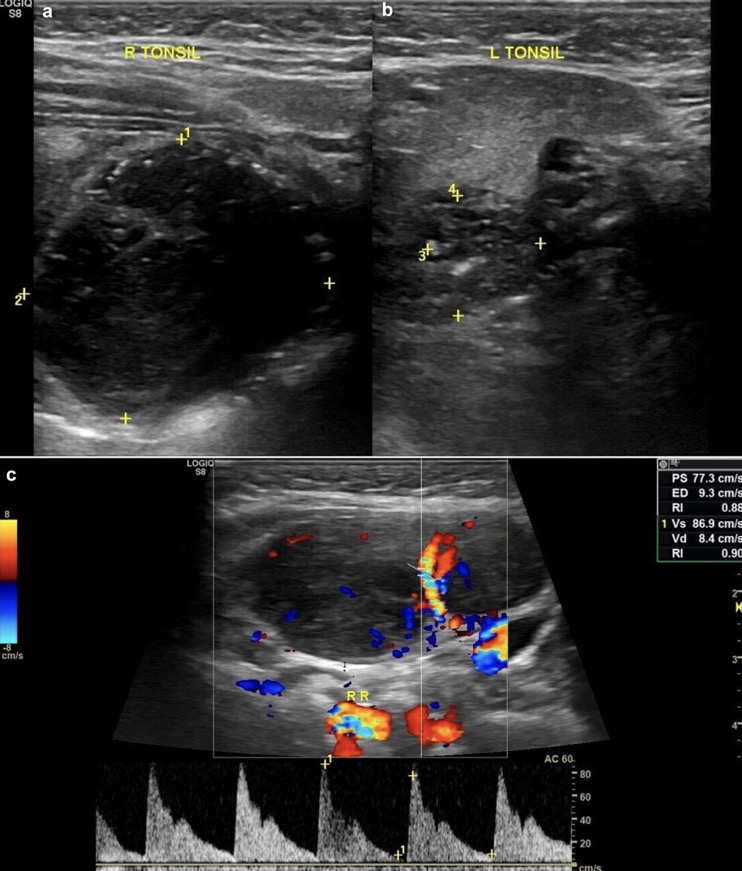

1. Asymétrie de la taille des amygdales (élargissement unilatéral)

2. Sphérique au lieu d'ovoïde

3. Altération de l'échotexture des amygdales

(A) Homogènement hypoéchogène

(B) Perte de son apparence striée

4. Augmentation de la vascularisation amygdalienne interne

5. Capsule amygdalienne bien définie mais sans limites lobulées régulières

EX: LYMPHOME DE BURKITT